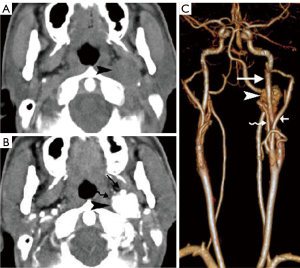

Paragangliomas have characteristic CT and MRI appearances based on their hypervascularity. They are usually homogeneously or heterogeneously hyperdense or hyperintense after contrast enhancement, with incorporation of adjacent arteries on CT and MRI (Figures 10-12) (12). On MRI, serpentine and punctate areas of signal void representing high vascular flow are interspersed with areas of high signal intensity caused by slowly flowing blood. This “salt-and-pepper” pattern is seen in all lesions greater than 2 cm in maximal dimension (Figure 11) (23-25). Carotid body tumors (paragangliomas of the carotid body) splay the ICA and the external carotid artery (ECA) and may encase the ICA and ECA (Figure 10), whereas vagal paragangliomas displace both ICA and ECA anteromedially, separating these vessels from the IJV (Figure 11). Paragangliomas may be multicentric and can manifest as unilateral or bilateral lesions, either simultaneously or sequentially. Only a very low percentage of 3% of paragangliomas will undergo malignant transformation (25). The presence of local lymph node involvement, distant metastases, or extensive local invasion will establish the malignancy of a paraganglioma.

In the past, digital subtraction angiography (DSA) played an important role as a first-line imaging investigation for paragangliomas (26). However, such an invasive method is reserved for those few patients whose diagnosis, after sectional imaging, remains inconclusive, or preoperative embolization. DSA, and sometimes computed tomography angiography (CTA), will show feeding arteries, such as the ascending pharyngeal artery (the artery of the paraganglioma) (Figure 12) and occipital artery (27). DSA also shows intense staining of the tumor and a rapid venous drainage.